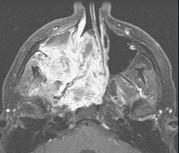

问题 15岁,男性,渐进性鼻塞1年余,MRI扫描如图所示,请选择最可能诊断()

选项 A.鼻咽部纤维血管瘤 B.鼻咽部脓肿 C.脊索瘤 D.鼻咽部囊肿 E.鼻咽癌

答案 A